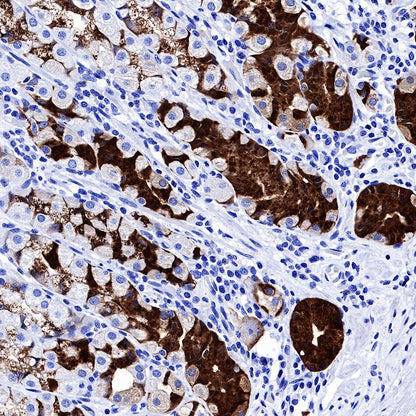

Negative control: IHC shows negative staining in paraffin-embedded human liver. Anti-PG II/PGC antibody was used at 1/1000 dilution, followed by a HRP Polymer for Mouse & Rabbit IgG (ready to use). Counterstained with hematoxylin. Heat mediated antigen retrieval with Tris/EDTA buffer pH9.0 was performed before commencing with IHC staining protocol.